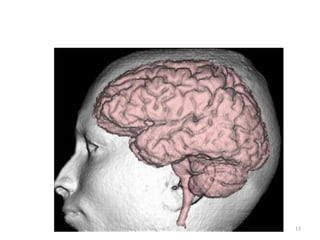

• Da região da cabeça, a área mais estuda é o

REVISÃO ANATÔMICA

vasculares, tumorais, deformidades e do

sistema nervoso central.

• Trata-se de uma região com grande riqueza

anatômica, necessitaríamos de muito tempo

para discutir todas. Vamos elencar as mais

importantes no desenvolvimento do exame.